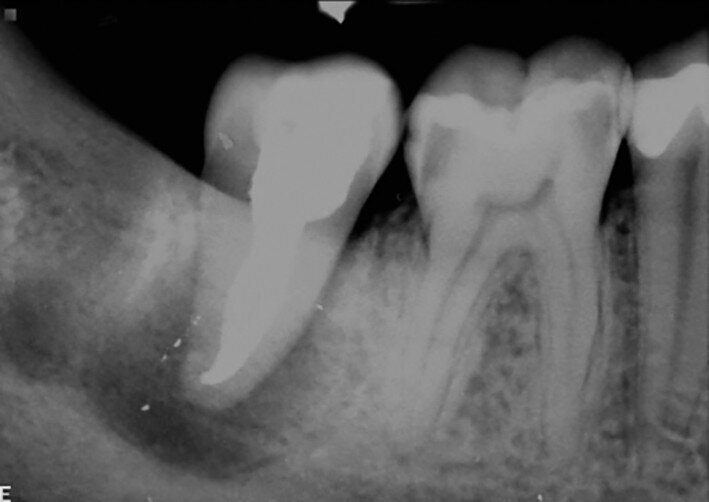

Fig. 19a: Radiographs: Pre-op periapical.

Fig. 19b: Radiographs: Immediately after transplantation.

Fig. 19c: Radiographs: One-year recall.

Fig. 19d: Radiographs: Two-year recall.

A 16-year-old female patient required extraction of a maxillary molar. Tooth #18 was transplanted to site #16. Root development was still continuing after two years (Figs. 19a–d).